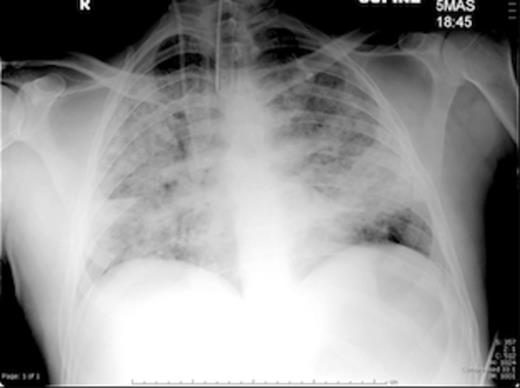

The patient was rapidly intubated and ventilated on ICU. A chest x-ray highlighted bilateral extensive acute respiratory distress syndrome (ARDS) (Figure 3). He continued to receive intravenous antibiotics, ionotropic support and nasogastric feeding. The orthopaedic team reviewed the patient daily and dressings were changed regularly.